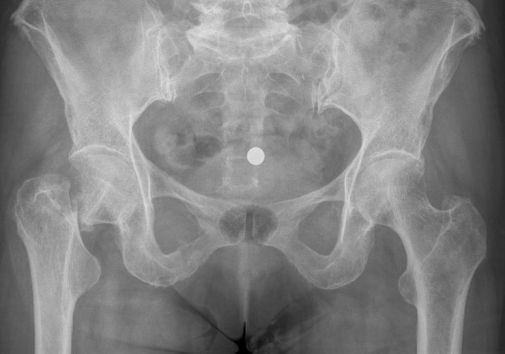

Een gebroken heup kenmerkt zich doordat de patiënt na de val niet meer op het aangedane been kan staan tgv pijn in de heup. Vaak is daarbij het been ook wat verkort ten opzichte van de andere kant en ligt de voet wat naar buiten gedraaid. Op de Spoedeisende hulp zal er een Röntgenfoto worden gemaakt om te kijken of en in welk gedeelte het bot is gebroken.

De behandeling van een gebroken heup is afhankelijk van de exacte plaats van de breuk en de stand van de breuk.

Operatie: in de meerderheid van de gevallen is er een indicatie voor operatie. Het doel van de operatie is de patiënt pijnvrij te krijgen en zo snel mogelijk weer uit bed te krijgen, aangezien patiënten snel zieker worden als ze alleen maar in bed kunnen blijven liggen (ontstaan van oa. longontstekingen en doorligplekken) Het soort operatie is afhankelijk van onder andere de leeftijd van de patiënt, de plaats van de breuk en de stand van de breuk. Als de breuk in de nek van de heup zit (vlak onder de kop), dan zal er gekozen worden voor het vastzetten van de heupkop met bijvoorbeeld 1 of meer stevige schroeven in de heupkop, of voor het vervangen van de heupkop met een heupprothese. Indien de breuk onder de nek en dus meer in het bovenbeen zit, zal er gekozen worden voor of een stevige schroef in een plaat, of voor een stevige schroef met een pen in het bovenbeensbot.